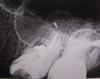

Альберта77 Опубликовано 22 марта, 2011 Автор Поделиться Опубликовано 22 марта, 2011 Выкладываю снимки (было и после лечения). Надеюсь, картина прояснится... Ссылка на комментарий

Dr.Ka Опубликовано 22 марта, 2011 Поделиться Опубликовано 22 марта, 2011 На снимках я красным выделила, в чем собственно проблема. На одном из корней - киста. Воспалительный процесс, который и привел к появлению кисты, обострился, поэтому появилось то, что Вы называете "флюсом" и боли. Совершенно верно то, что были пролечены каналы. Прошли ли боли после пломбировки каналов? Если нет, то каналы нужно перелечивать. Если да, то боли могут быть из-за выведения большого количества пломбировочного материала в полость кисты. Тогда только одно - ждать и наблюдать. А для разреза оснований в данный момент действительно нет.http://s55.radikal.ru/i150/1103/c1/ea47e0454e68.jpghttp://i039.radikal.ru/1103/ce/e0fb00350aa0.jpg Ссылка на комментарий

Альберта77 Опубликовано 22 марта, 2011 Автор Поделиться Опубликовано 22 марта, 2011 Спасибо за ответ. Но на втором снимке не киста. Это врач пасту лечебную закладывала и направила на рентген, чтобы убедиться, до конца прошла в канале. Зуб меня сейчас абсолютно не беспокоит. Только нарыв на десне. Ссылка на комментарий

Dr.Ka Опубликовано 22 марта, 2011 Поделиться Опубликовано 22 марта, 2011 Киста за неделю никуда не делась. Хорошо если она через месяцев 10-12 исчезнет. Так что на втором снимке - киста, заполненная пастой. Если микрофлора, вызвавшая появление кисты, убита при лечении канала, "нарыв" пройдет и всё наладится. Если нет, антибиотики помогут вряд ли. Ссылка на комментарий

DokDent Опубликовано 22 марта, 2011 Поделиться Опубликовано 22 марта, 2011 Спасибо за ответ. Но на втором снимке не киста. Это врач пасту лечебную закладывала и направила на рентген, чтобы убедиться, до конца прошла в канале. Зуб меня сейчас абсолютно не беспокоит. Только нарыв на десне.За пределы корня (канала) ничего выходить не должно.Даже если это лечебная паста.Возможно образование отверстия в Вашем уплотнении (свища),через которое выведется избыток материала,либо это сделает хирург.Возможно рассасывание,но реже. Ссылка на комментарий